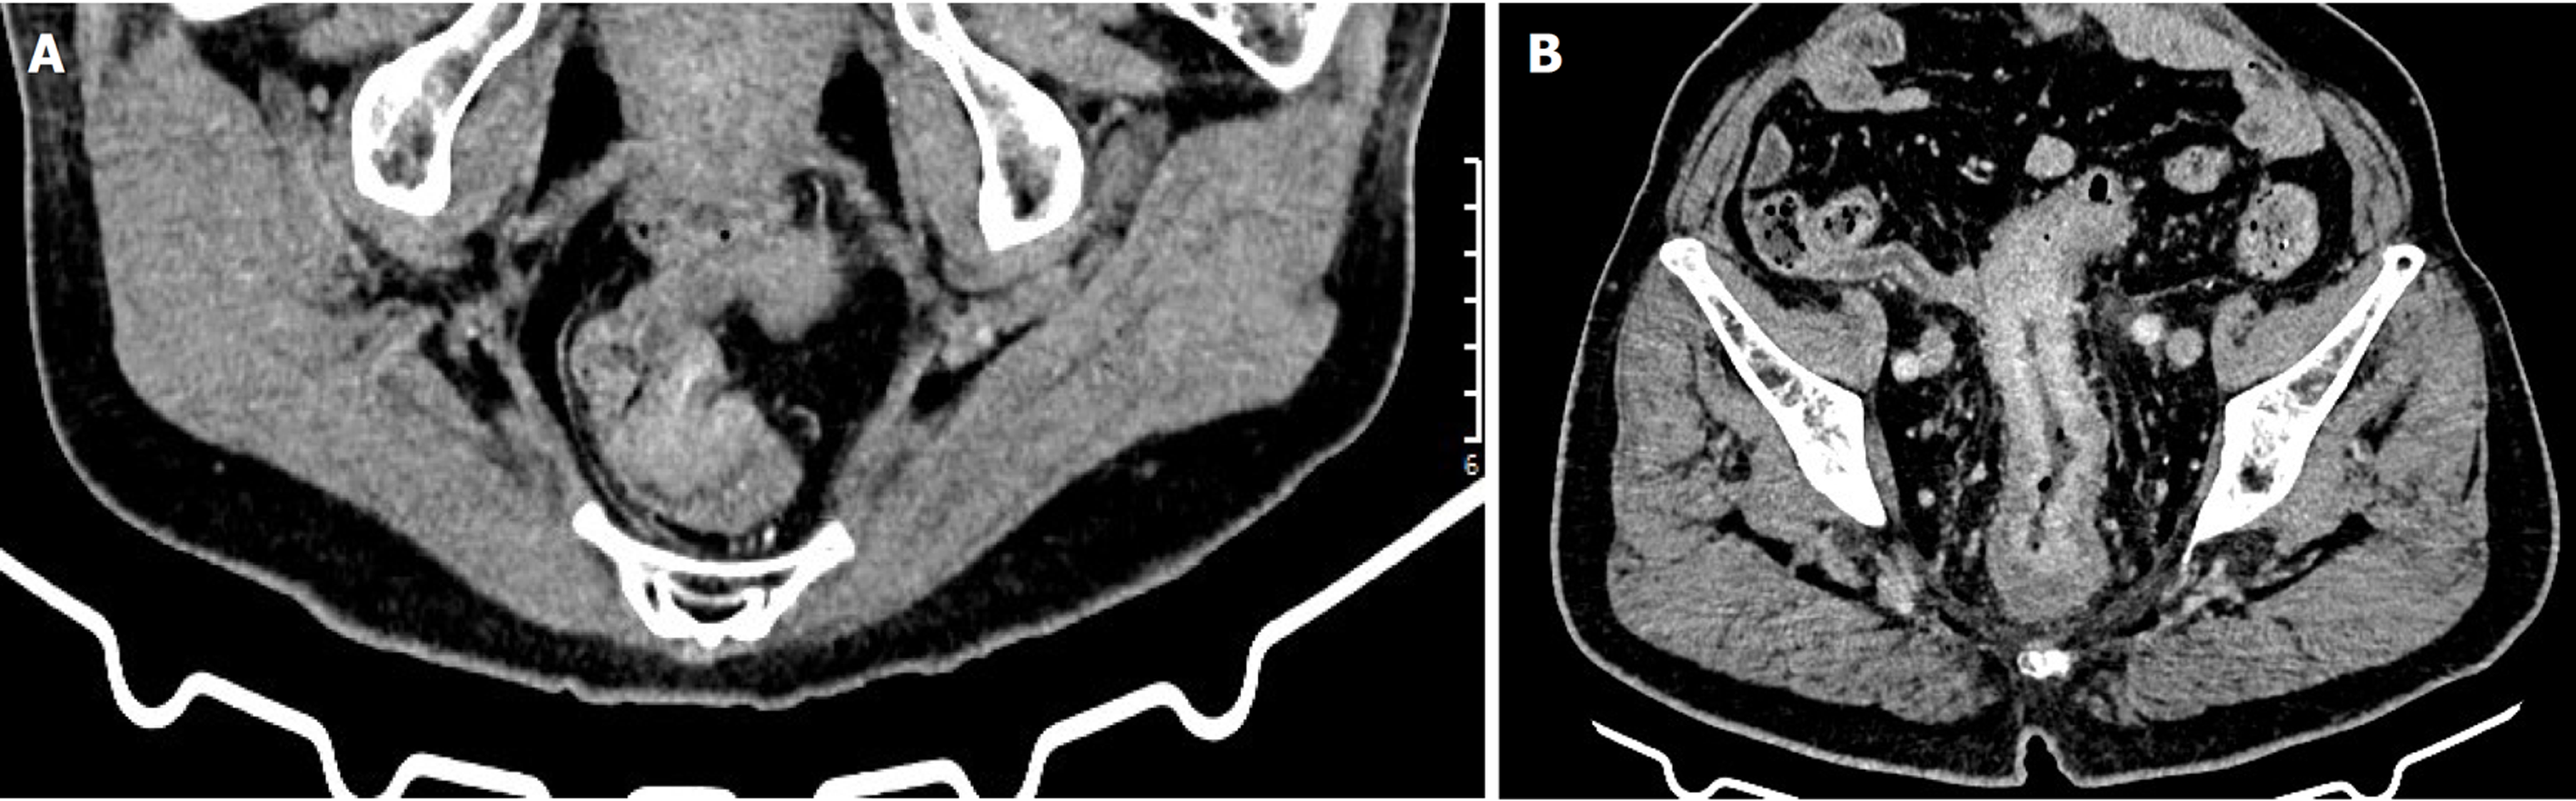

两组CEA、CA19-9、平扫CT值、动脉期CT值、静脉期CT值、动脉期CT强化值、静脉期CT强化值、强化CT值比较, 差异具有统计学意义(P<0.05); 两组年龄、性别、高血压、糖尿病、大体病理分型、肿瘤直径、分化程度、T分期、N分期、CA125、强化形式、肿瘤部位、增厚形式(评估方法1、评估方法2)、脉管瘤栓、神经侵犯、管腔狭窄、周围脂肪间隙、腹水比较, 差异均无统计学意义(P>0.05). 见表1, 经典增强CT图像见图1.

增强CT是结直肠癌患者治疗前常规检查和术后随访的首选影像检查方法, 通过注射造影剂, 在CT扫描时可观察患者造影剂分布, 清晰地呈现肿瘤形态、位置、大小及周围血供, 能准确判断结直肠癌局部侵犯、肝脏及胸部等转移[18-20]. 本研究基于增强CT特征, 发现动脉期CT强化值、静脉期CT强化值、强化CT值是结直肠癌患者预后不良的影响因素, 分析原因可能是由于动脉期CT强化值是评估注射对比剂后25-30 s变化, 反映肿瘤新生血管密度, 静脉期CT强化值主要评估注射对比剂后60-70 s变化, 主要反映肿瘤实质强化情况, 强化CT值是注射对比剂后, 肿瘤组织CT值相对于平扫的增加值, 主要反映肿瘤组织血供丰富情况和肿瘤血管通透性, 动脉期CT强化值、静脉期CT强化值、强化CT值升高说明结直肠癌患者新生血管密度较大, 病灶内部有丰富血管, 为肿瘤细胞生长提供营养和氧气, 肿瘤细胞进入快速生长阶段, 促进肿瘤细胞增殖分化、迁移和侵袭, 进而影响患者预后[21-23]. 基于上述影响因素构建结直肠癌患者预后的列线图, 验证结果显示, 该模型具有良好的预测效能和正向净收益.